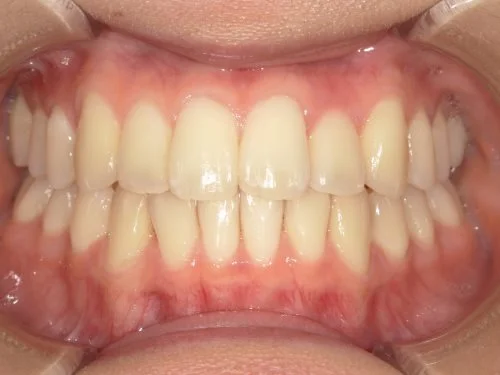

<症例7>歯がガタガタで噛み合わせが悪くお悩み

抜歯無し・マウスピースのみで矯正した症例です。

もともと歯列弓が非常に狭く、V字に近い形をしていたので噛み合わせも非常に不安定でした。

また、下顎前歯部がかなり上の方に生えていたため、下の前歯が上の前歯を突き上げてしまい出っ歯の状態になっていました。

現在では見た目はもちろん、臼歯の噛み合わせも改善しております。

患者様と症状

主訴:歯のガタガタ、噛み合わせが悪い

性別・年齢:20代女性

問題点:叢生(重度)、V字歯列弓、ディープバイト

診断:前歯部の叢生を伴うアングルⅠ級、骨格性Ⅰ級の不正咬合

主なリスク:臼歯の移動に伴い一時的に咬合しにくくなる、歯肉退縮

症状:叢生(そうせい) 過蓋咬合(かがいこうごう)

治療内容

治療期間:1年10ヶ月

治療費用:990,000円(税込)

プラン:Full2プラン

抜歯:無し

再診治療費:無し

追加治療費:無し

保定装置費:無し

治療前後の写真